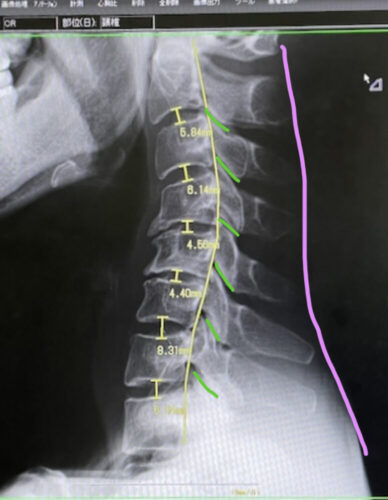

恥ずかしながら、わたしの首には、

自然は前弯(前のカーブ)が

ほとんどありませんでした

今は、どうかな〜?

(…というか、むしろ後弯してる💦)

そのために衝撃がうまく分散できずに

振動やズレがダイレクトに

頭に伝わります

首のカーブが足りてない

そんな自覚があったなら